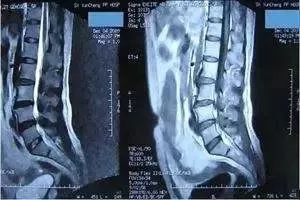

CT最常用在头部、胸部、腹部和脊柱疾病等方面的检查,有些四肢和骨骼问题用X线检查看不清楚时,也可以选择做CT。目前体检项目中的CT主要是胸部CT,用于早期肺癌筛查。

磁共振可以检查的部位很多,包括脑部、血管、肌肉、韧带、脊柱等等,但是建议在有症状或医生建议下做磁共振检查,正常的体检作为疾病的初期筛查,通常没有必要做磁共振。